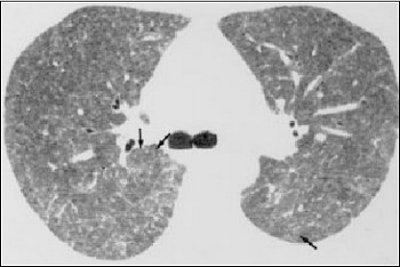

The same holds true for CT and thoracic injuries, according to Dr. Masanori Akira and colleagues in their Radiology paper. On high-resolution CT, the most common findings of NSAID-related lung disease may be areas of ground-glass opacity with interstitial thickening and centrilobular opacities, Akira told AuntMinnie.com, "noting that these areas reflect the allergic reaction. Some patients may show peripheral consolidation and drug-induced eosinophilic pneumonia, while others may have non-cardiogenic pulmonary edema. The best imaging modality for identifying NSAIDs-related lung disease is high-resolution CT."

![]() |

| Fifty-two-year-old man with hypersensitivity reaction; patient was receiving methotrexate for rheumatoid arthritis. High-resolution CT scan shows poorly defined centrilobular nodules (arrows) and extensive areas of ground-glass attenuation. Differential diagnosis includes interstitial pneumonitis related to rheumatoid arthritis, opportunistic infection, and adverse drug reaction. Diagnosis was confirmed at open lung biopsy. Ellis SJ, Cleverley JR, Müller NL, "Drug-induced lung disease: high-resolution CT findings (AJR 2000, Vol.175, pp.1022-1027). |

Regardless of the imaging modality used, Akira cautioned that when it comes to tracking NSAIDS injuries, no two are alike.

"The imaging findings of drug-induced lung disease vary among patients and drugs," he warned. "The same drug may produce more than one pattern."